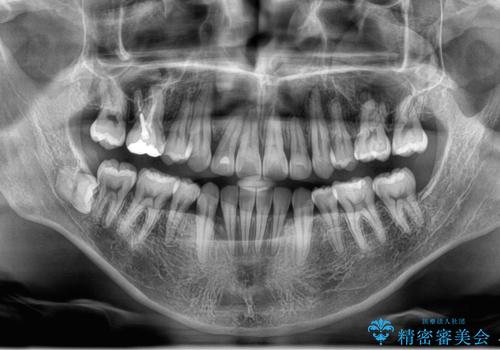

骨格的に上顎骨が小さいために相対的に下顎骨が前に出ていたため、歯の傾きなど理想的な仕上がりが難しく、外科矯正ではなく歯列矯正の場合はカモフラージュ矯正になること説明の上、矯正治療を進めることになりました。

上顎は左右5番抜歯、下顎は左右4番抜歯しています。

途中までは下顎は全体にワイヤーをはらずに、セクショナルワイヤーにて治療を進めています。

上顎は最初から全体にワイヤーをはっていましたが、上顎前歯部の歯肉退縮のリスクが高そうだったために、途中まで下顎と同じくセクショナルワイヤーで進めています。

八重歯(3番)などは歯肉移植も検討できればよいかなと思います。